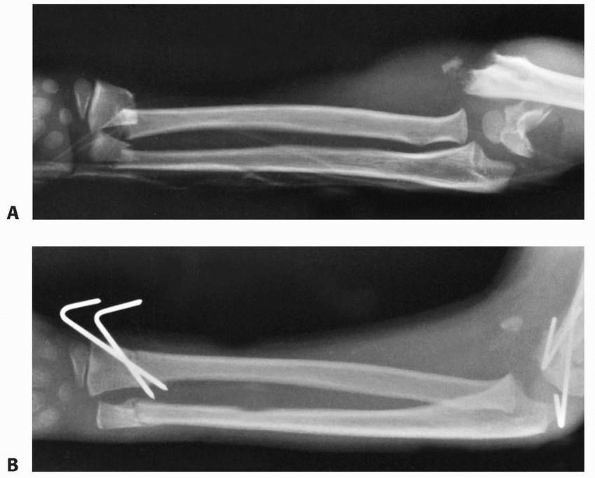

FIGURE 9-32 A. The appearance of the distal ulna in the patient seen in Figure 9-21,

3 years after injury, demonstrating premature fusion of the distal ulnar physis with 3.2 cm of shortening. The distal radius is secondarily deformed, with tilting and translocation toward the ulna. B. In the patient in Figure 9-21 with distal ulnar physeal arrest, a lengthening of the distal ulna was performed using a small unipolar distracting device. The ulna was slightly overlengthened to compensate for some subsequent growth of the distal radius. C. Six months after the lengthening osteotomy, there is some deformity of the distal ulna, but good restoration of length has been achieved. The distal radial epiphyseal tilt has corrected somewhat, and the patient has asymptomatic supination and pronation to 75 degrees. D. Similar case to Figure 9-32A-C, but with more progressive distal radial deformity treated with corrective osteotomy and epiphysiodesis of the distal radius. |

radial closing wedge osteotomy, and ulnar lengthening (Fig. 9-32),12,81,152